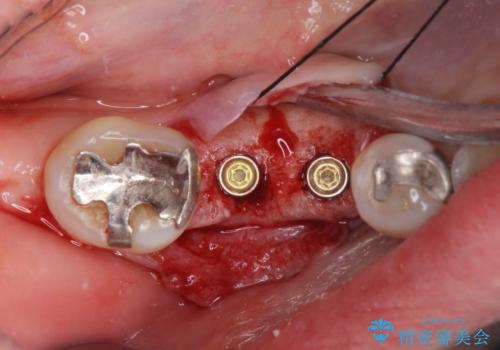

保存できない状態でしたので抜歯をして歯槽堤保存術を行いました。その後大臼歯部にインプラント治療を行いました。

欠損部に1本だけインプラントを埋入しても大きな被せ物になってしまい清掃性が悪くなるので清掃性が良くなるように2本小臼歯用のインプラントを埋入しました。

- 抜歯、歯槽堤保存術・11万円 インプラント体、アバット、仮歯、ジルコニアクラウン・42.9万円×2 骨造成・5.5万円 e-maxインレー・7.7万円 費用は治療当時の料金となります